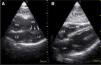

En los estados hipovolémicos el área de fin de diástole es inferior a lo normal en cambio en estados hiperdinámicos es normal. A continuación en la figura 20 se observan un VI con hipovolemia y un VI hiperdinámico.

Para diferenciar hipovolemia de hiperdinamia cuando no se puede evaluar VCI hay que evaluar el área de fin de diástole en eje corto para-esternal de VI.